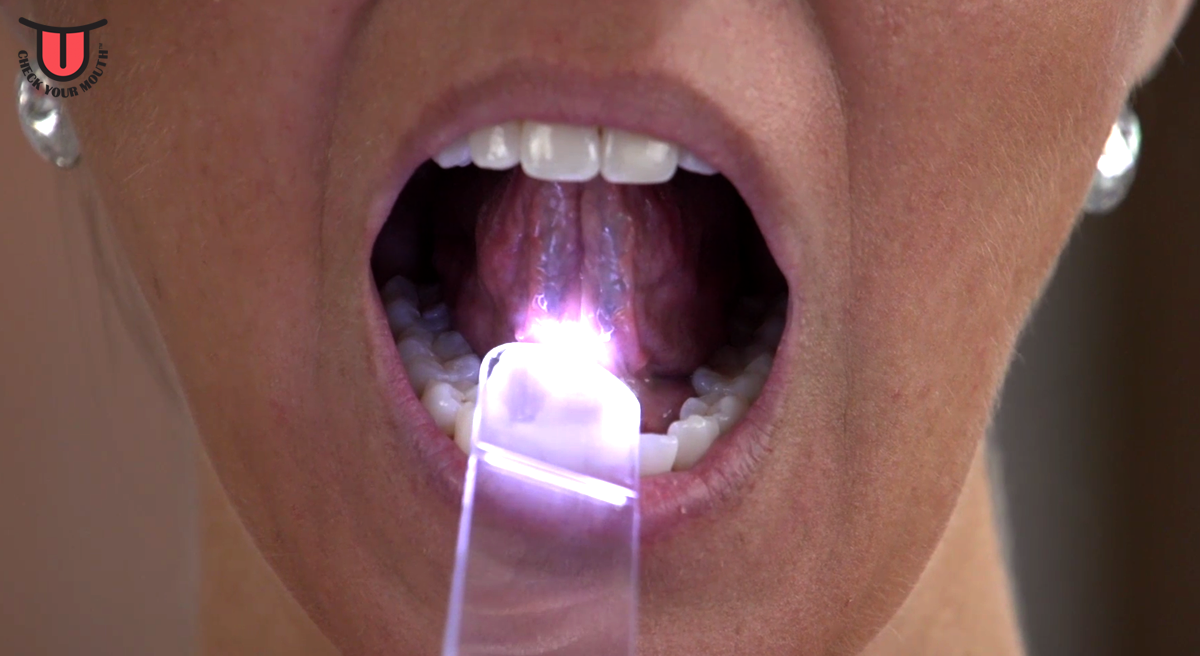

Six Step Screening Eva Grayzel

Self Oral Cancer Screening Socs Education Program School

10 Steps To Perform An Oral Cancer Screening Dentistryiq

Oral Cancer Screening At Freedom Dental Melbourne

Introduction Check Your Mouth

Self Oral Cancer Screening Socs Education Program School

Making Oral Cancer Screening A Routine Part Of Your Patient

Introduction Check Your Mouth

Self Oral Cancer Screening Socs Education Program School

Faces Of Oral Cancer Six Step Screening

Self Oral Cancer Screening Socs Education Program School

Self Oral Cancer Screening Socs Education Program School